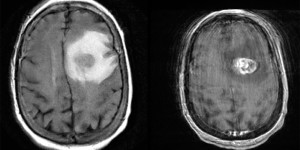

- Imaging: Contrast ring-enhancing lesions with significant vasogenic edema. Lesions can also have internal necrosis and can extend through the corpus callosum (butterfly lesion).

- Astrocytoma, IDH-mutant (grades 2-4)

- Pathology: Cells with increased mitotic activity with pseudopalisading necrosis and microvascular endothelial proliferation.

- Treatment: Maximal safe resection followed by intensity-modulated radiation therapy (IMRT) plus concomitant temozolomide (alkylating chemotherapy) followed by adjuvant temozolomide.

- Methylation of the MGMT gene is associated with better treatment response to temozolomide.